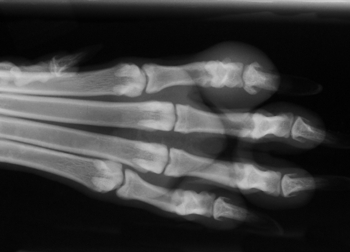

일반 X-Ray 촬영검사

흉부, 복부, 두부, 근골격계, 척추 촬영을 통해 환자 전반에 걸친 기본적인 정보를 획득할 수 있는 손쉬운 진단방법입니다. 본원 영상의학과의 X-선 검사장비는 디지털 검사장비를 도입하여 영상의 구현과 검사시간을 단축하였으며, 촬영시간은 물론 촬영 대기시간, 촬영에서 진단까지의 시간이 단축되어 환자 서비스 향상을 이룰 수 있습니다. 만일 촬영 후에 사진이 만족스럽지 않은 경우라 하더라도 촬영 후에 농도조정이 가능하기 때문에 불필요한 재촬영을 대폭 줄일 수 있습니다.